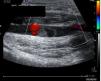

Figure 2.

Partial occupation of the axillary vein by a segment of approximately 40mm.

The suspected diagnosis was a probable rotator cuff injury but, due to the striking clinical manifestations, the following complementary tests were carried out: analytical tests, of which we include and highlight D-Dimer assay 309ng/ml, correlated with the Wells score, with high probability of thrombosis (score3), fibrinogen 480mg/dl, 100% prothrombin activity 100%, CPK 421<IU/l, CPR 1.6mg/dl; as well as shoulder ultrasound and upper limb venous Doppler ultrasound. The ultrasound findings were described as destructuring of the muscle fibres and increase in volume of the proximal and middle third of the biceps brachii in relation to extensive fibrillar tear with associated haematoma of 6cm and tendon of the long portion of the biceps with thickening and free fluid, compatible with partial tear (Fig. 1). In addition, occupation of the partial axillary vein in a segment of some 40mm compatible with thrombosis (Fig. 2). Permeable internal jugular, subclavian, humeral, basilic and cephalic vein, with no signs of DVT.